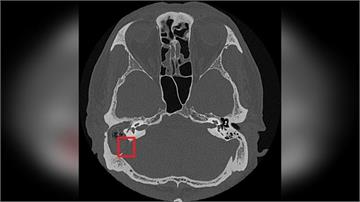

{PLAYICON}慢性中耳炎勿輕忽!小心併發膽脂瘤造成聽力與神經損傷